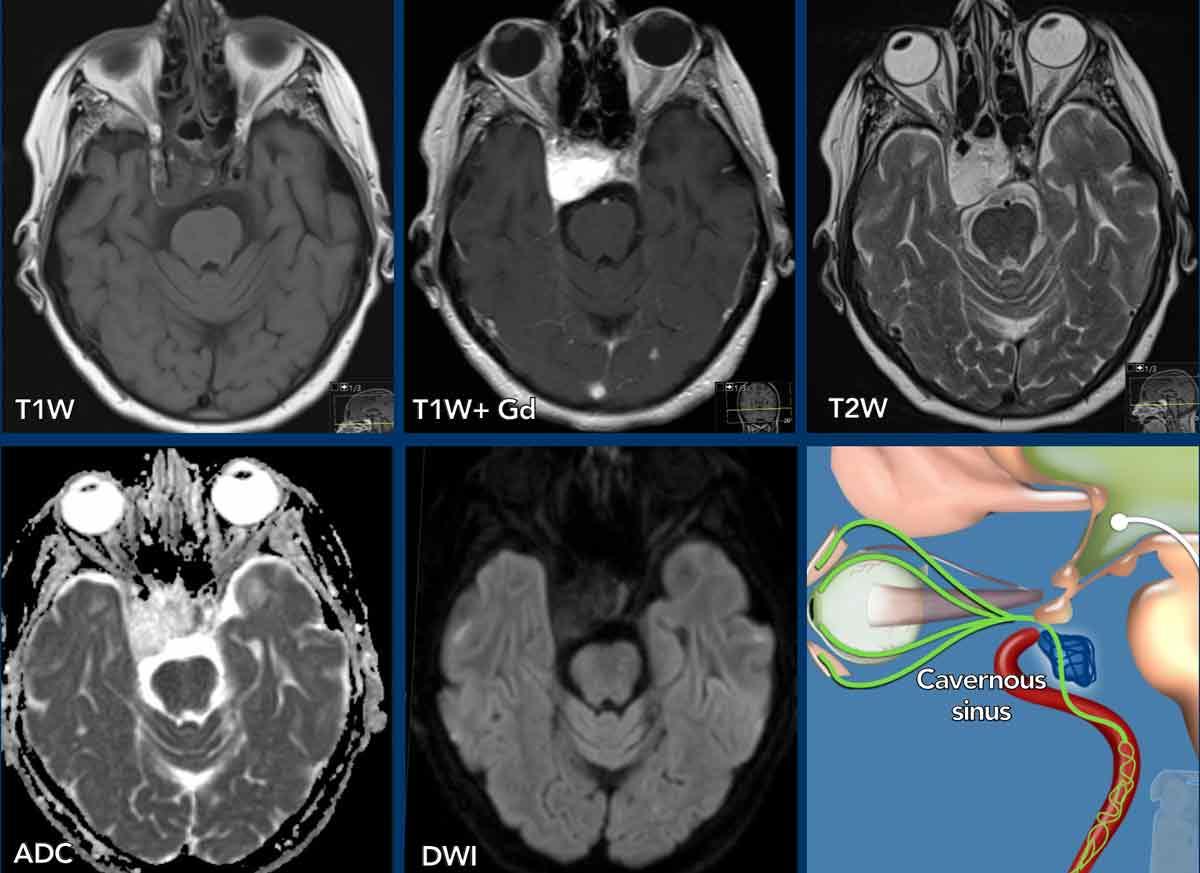

Ca lâm sàng

Những hình ảnh này của một phụ nữ 79 tuổi không thể được thăm khám đúng cách do bệnh nhân nằm ở tư thế bào thai và run rẩy dữ dội.

Bệnh nhân cũng có hội chứng Horner bên phải, nhưng điều này được chẩn đoán muộn hơn, điều này không hiếm gặp như chúng tôi đã đề cập trước đây.

Do tình trạng lâm sàng của bệnh nhân, chụp CT được ưu tiên hơn so với chụp MRI.

Đầu tiên hãy xem xét CT.

Những phát hiện là gì và chẩn đoán phân biệt của bạn là gì?

Hình ảnh

Tổn thương dạng khối ở bên phải tại vị trí xoang hang.

Tổn thương chứa thành phần mỡ

Thảo luận

Dựa trên sự hiện diện của mô mỡ trong tổn thương, chẩn đoán phân biệt được đặt ra là nang bì và u máu.

Continue with the MRI…

Các hình ảnh MR cho thấy mô mỡ nằm bên trong khối u và đây không phải là mô mỡ bình thường mà chúng ta đôi khi thấy bao quanh xoang hang.

Bệnh nhân này đã được phẫu thuật và chẩn đoán cuối cùng là u máu.